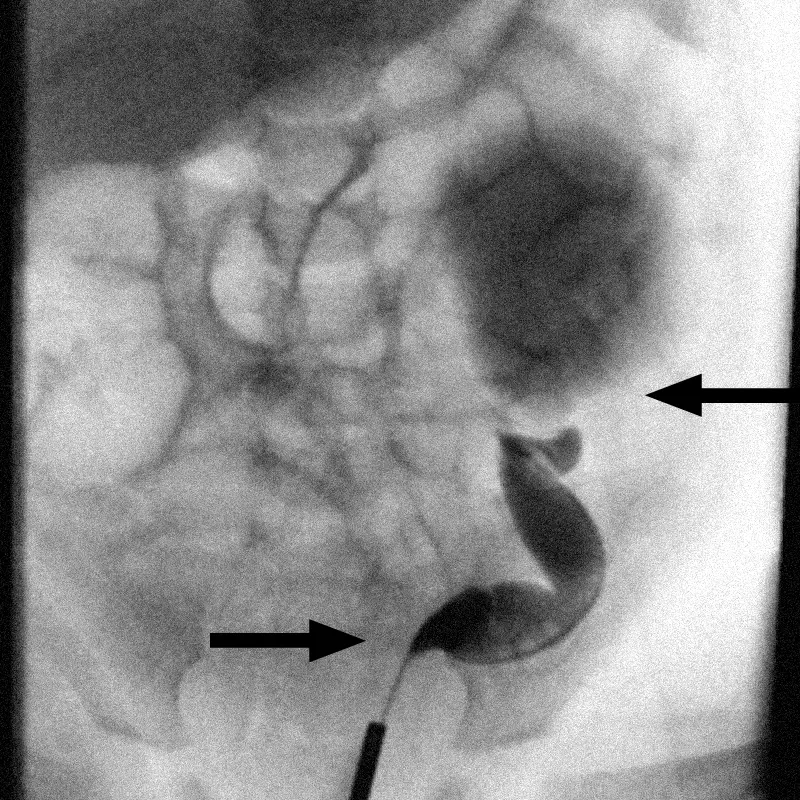

Contrast-enhanced imaging reveals fluid buildup and bilateral ureteral obstruction in the kidneys.

After Isaac was born that July, doctors from Pediatric Nephrology and Pediatric Urology met to discuss his options and started him on early prophylactic antibiotics. When Isaac was three months old, they brought him in for X-rays and confirmed his bilateral severe hydronephrosis, or double obstruction of the ureters at the level of the bladder and kidney.

Because of the complexity and Isaac’s small size as an infant, the team proceeded with a staged reconstructive approach, addressing one ureter at a time to minimize risk and support recovery. Radiology provided anatomical mapping, and nephrology monitored renal function to ensure preservation of parenchyma, or functional tissue of the kidneys.